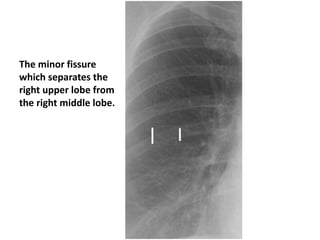

Fissures : they become wide if there is fluid

The minor fissure

which separates the

right upper lobe from

the right middle lobe.